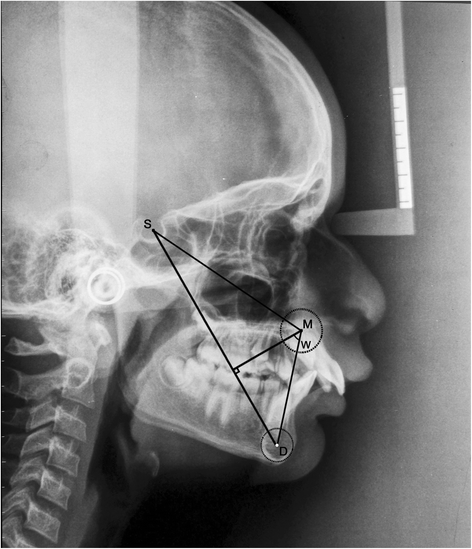

The pre-treatment and post-functional lateral cephalograms of 25 subjects (17 males, 8 females) with class II division 1 malocclusion treated with twin block functional appliance were selected. Five angular (ANB, β angle, APDI, YEN angle, W angle) and two linear (Wits analysis, App-Bpp) parameters were traced on both sets of cephalograms. Paired Student’s t-test, one-way ANOVA, post hoc test, and Karl Pearson correlation statistical analysis were performed.

The angular parameters used were as follows (Table 1):

The linear parameters used were as follows (Figure 6, Table 1):

According to Tables 4 and 5, it is suggested that either the YEN angle or W angle can be used to assess skeletal anteroposterior discrepancy (mean difference = −0.6, p = 0.982, r = 0.894). With reference to the YEN angle, jaw rotations due to growth and treatment can mask true skeletal dysplasia [25]. The YEN angle requires accurate tracing of the premaxilla for its assessment. The W angle also requires accurate tracing of the premaxilla and locating its center, which is difficult. Also, determining which of the jaws is prognathic or retrognathic is difficult [12]. Thus, when accurate tracing of the premaxilla for the assessment of the W angle and YEN angle is not possible, the β angle can be used as it shows least correlation with the YEN angle and W angle (Tables 4 and 5).

No significant change in the mean of the difference between T1 and T2 values of the β angle and APDI was found (mean difference = 0.8, p = 0.927, r = 0.455) (Tables 4 and 5). The β angle uses the condylion as a reference point, but its identification on a closed mouth lateral cephalogram is difficult [26-28]. Thus, APDI can be used in lieu of the β angle when locating the condylion is difficult.